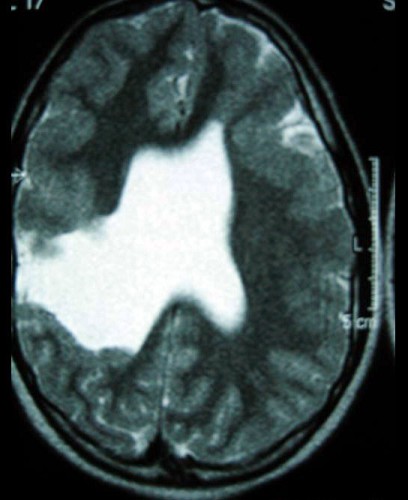

9岁男孩,有癫痫发作史,MR表现如图,首先考虑以下哪个疾病 ( ) TLC-00501.jpg TLC-00502.jpg TLC-00503.jpg TLC-00504.jpg

• A.胼胝体发育不全

• B.脑灰质异位

• C.Dandy-Walker综合征

• D.脑裂畸形

• E.无脑回畸形